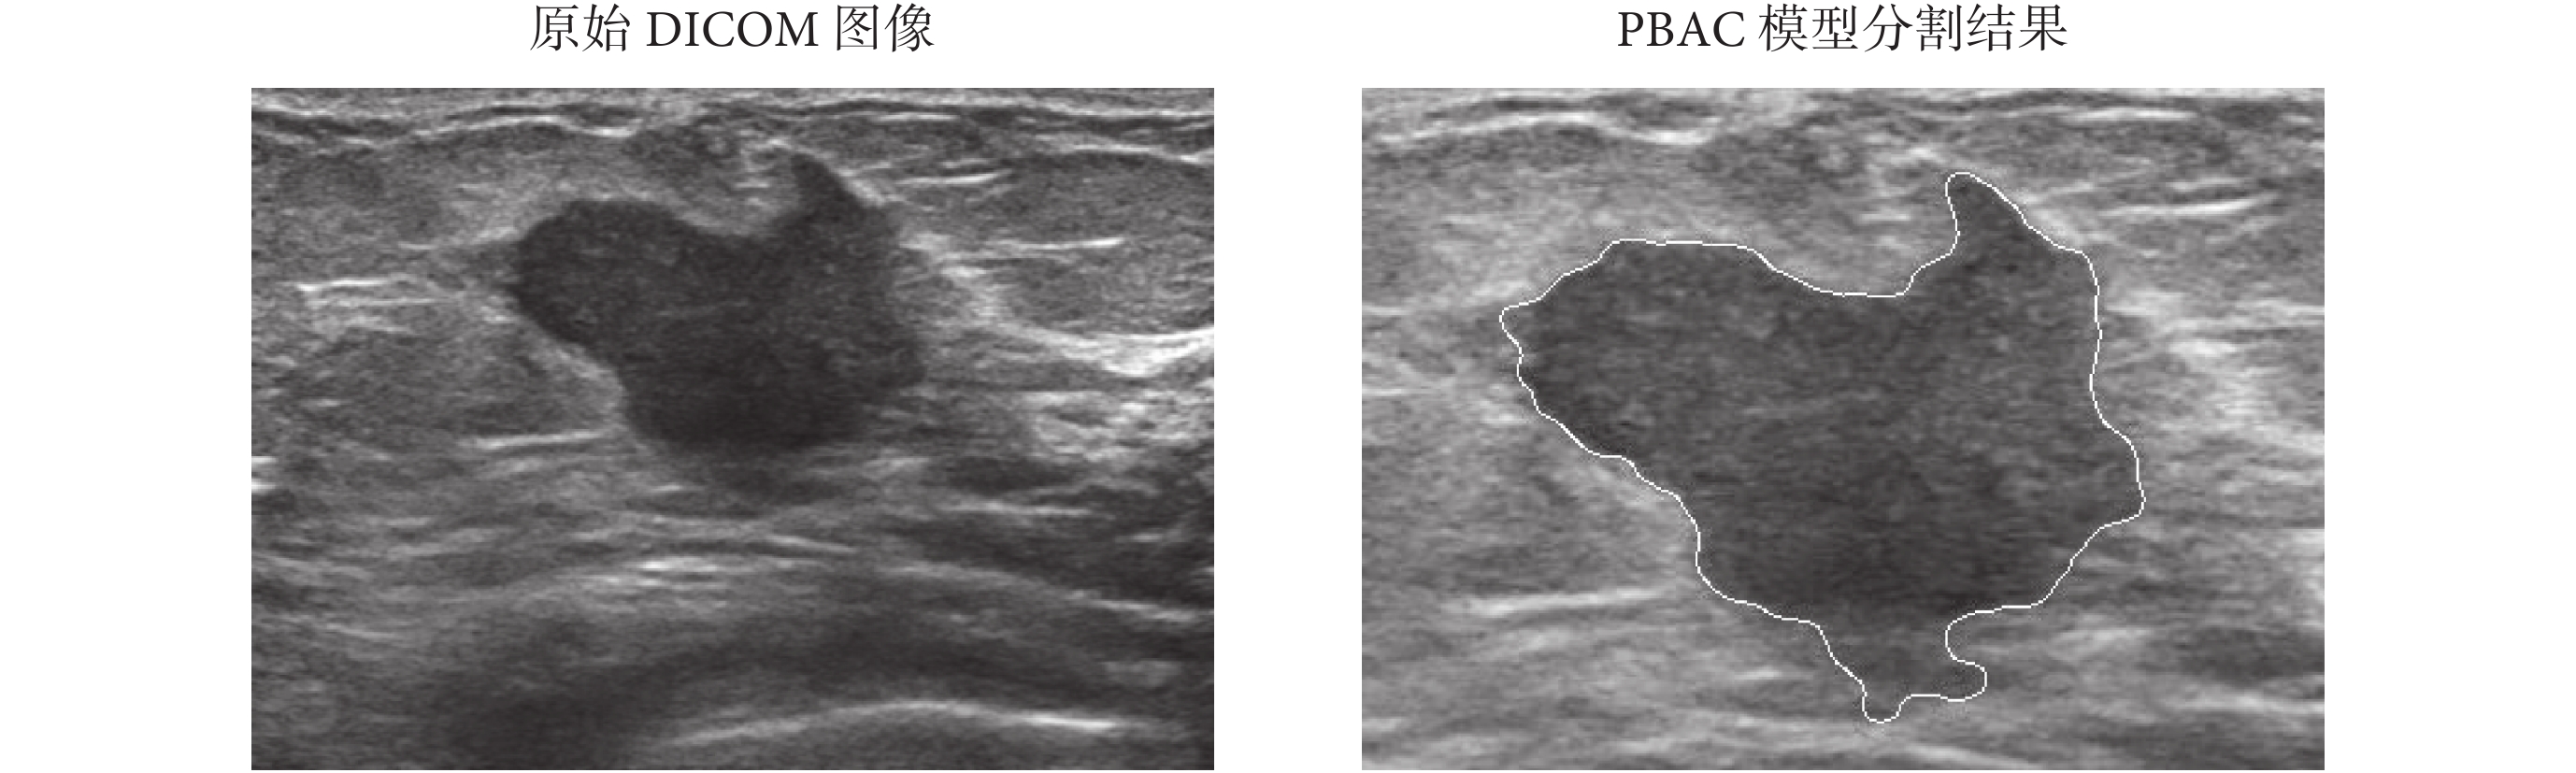

首先對 104 例乳腺腫瘤超聲圖像進行分割處理。原始圖像為 DICOM 圖像,先進行感興趣區域(region of interest,ROI)選取,然后進行自動分割。由有經驗的醫生判斷分割結果是否準確,對于自動分割結果準確性較差的圖像進行手動分割,104 例數據中 61.54% 為采用 PBAC 自動分割,38.46% 采用手動分割結果。作為例子,圖 2 為一例惡性乳腺腫瘤圖像測試算法效果。實驗結果說明 PBAC 模型的分割效果較好。